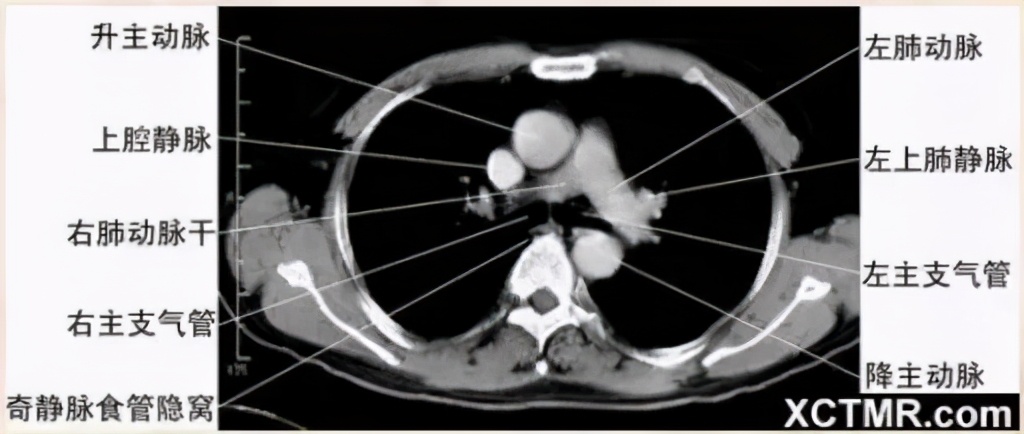

右肺动脉层面